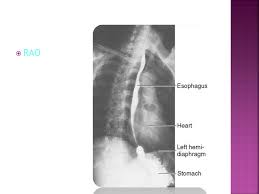

Normal Indentations On The Esophagus In Barium Swallow Right Anterior Oblique View Chest X Ray Pg Blazer